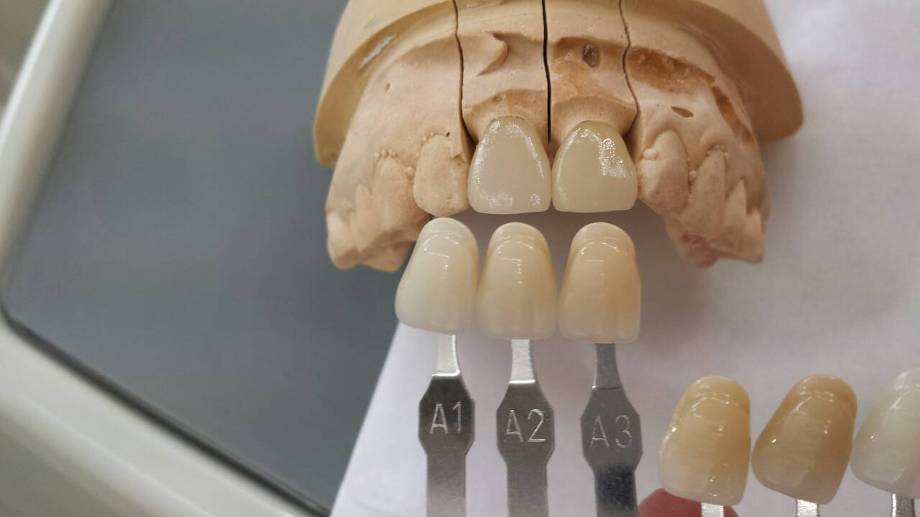

みなさんご存じのとおり、平成26年4月1日より「消費税」が5%から8%に増税になります。それに伴い、材料費用、技工費用などすべてに関して増税の対象となりそうです。

そこで![]() 当クリニックでも保険適応外の被せもの、詰め物、入れ歯、審美、矯正、ホワイトニングなどの「自費治療」に関しては、4月1日より消費税8%に変更となります

当クリニックでも保険適応外の被せもの、詰め物、入れ歯、審美、矯正、ホワイトニングなどの「自費治療」に関しては、4月1日より消費税8%に変更となります![]()

![]() セラミックやハイブリッドなどの白い歯

セラミックやハイブリッドなどの白い歯

![]() 白い歯の詰め物やかぶせ物を入れる審美歯科

白い歯の詰め物やかぶせ物を入れる審美歯科